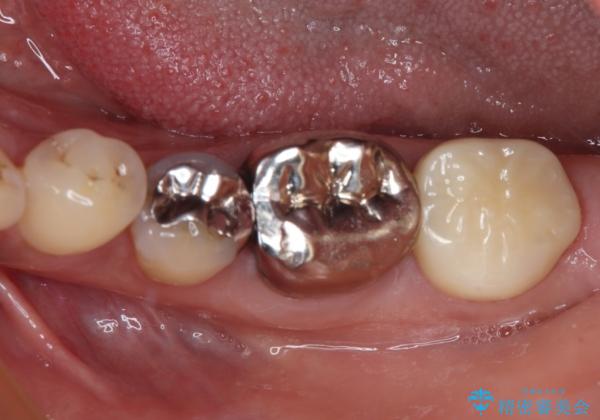

- 銀歯の奥が欠けてしまったとのことで来院された患者様です。

大きな銀歯が装着されており、その下からむし歯が広がっている状態でした。

特に症状はなく、神経組織も健全な状態であったため、むし歯を全て取り切った後にフルジルコニアクラウンにて補綴することとしました。